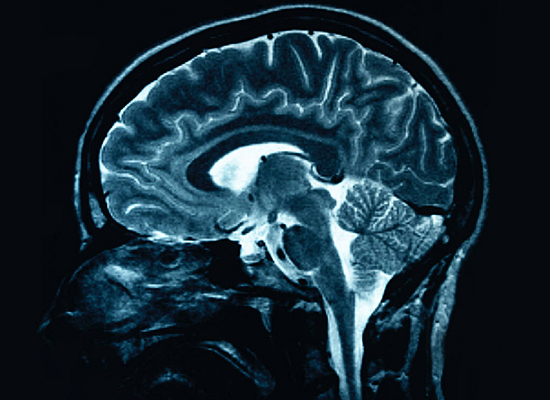

4. Anterográd amnézia (események elfelejtése)

3. Prozopagnózia (arcvakság)